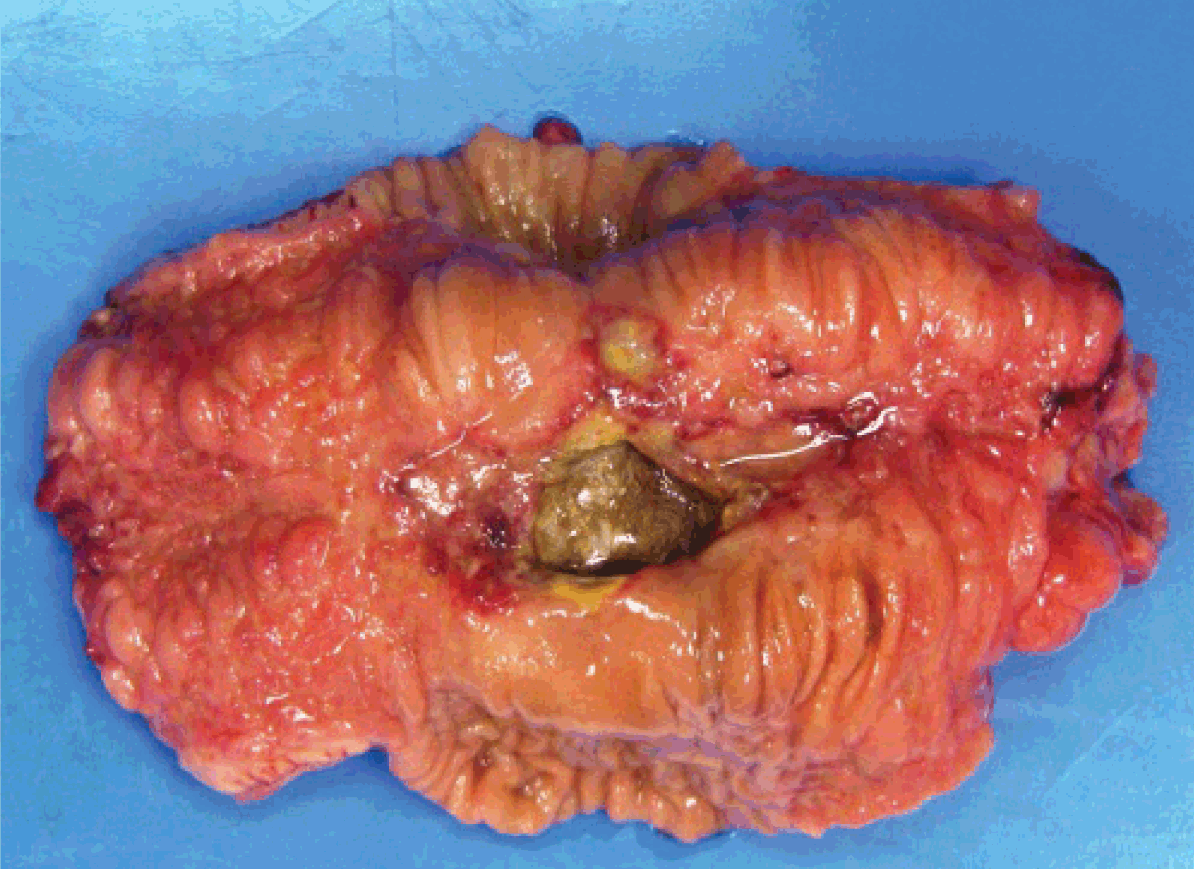

The patient was taken for exploratory laparotomy. A perforated loop of jejunum was located 80 cm distal to the ligament of Treitz. (Figure 2) Solid unmasticated mushrooms were found adjacent to the perforation. (Figure 3) The segment was resected and then primary jejunal anastamosis was performed.

Gross examination of the respected intestine demonstrated a diseased segment measuring 3.3 cm. A perforation measuring 2.8x1.5 cm was located in this segment. The lumen appeared somewhat smaller in the diseased portion of the bowel with a thickened wall and showed some mucosal ulceration. The diseased thickened portion had a hyperemic mucosa and a cobble stone appearance. (Figure 4) The remainder of the bowel appeared to be normal.

Figure 2: Surgically resected specimen illustrating perforated loop of jejunum.